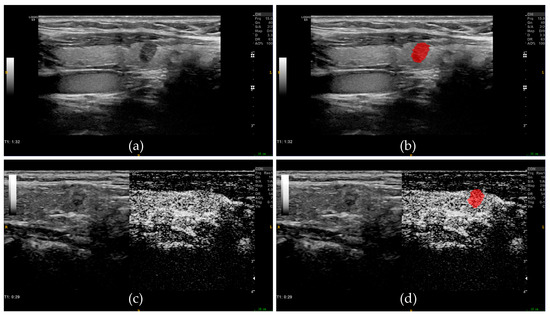

2.4. Image Segmentation and Feature Extraction